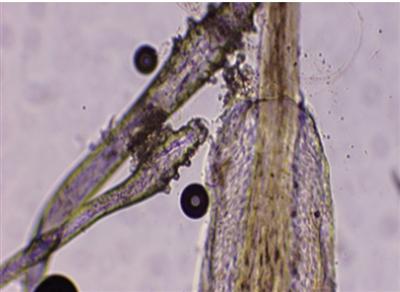

显微镜下,患者睫毛上的螨虫(白圈内)明晰可见。 病院供图

王女士等于其中一位。“眼睛反复发痒,一直观得是过敏,滴了眼药水也时好时坏,没念念到竟是睫毛上长了螨虫!”王女士在浙江省东谈主民病院眼科中心就诊时,看着查验屏幕上睫毛上密密匝匝附着的螨虫,既骇怪又困惑。